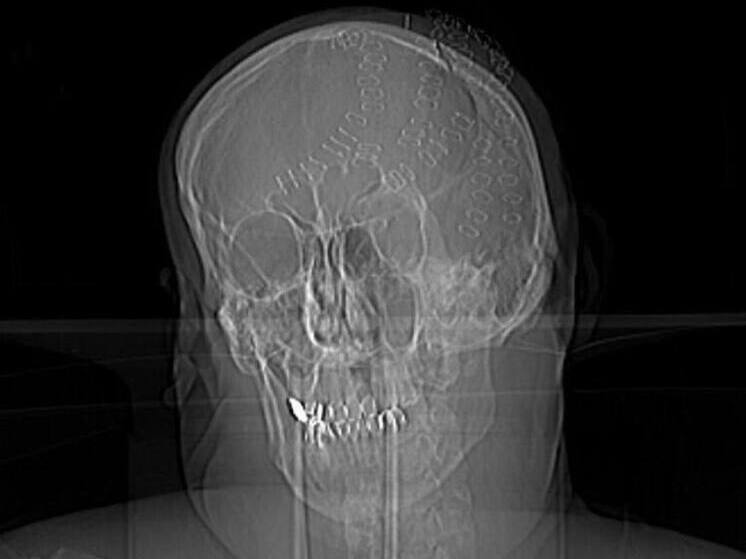

Врачи нейрохирургического отделения Владивостокской клинической больницы №2 провели уникальную операцию по спасению 50-летнего мужчины, получившего тяжелейшую травму головы в результате удара топором на острове Попова. Об этом сообщили в пресс-службе учреждения.

По данным медиков, у пострадавшего были зафиксированы травматическое субарахноидальное кровоизлияние, ушиб мозга, множественные оскольчатые и линейные вдавленные переломы теменных костей, а также рубленые раны головы. Пострадавший в критическом состоянии был эвакуирован катером и доставлен во Владивосток, где его уже ожидала бригада скорой помощи.

Состояние мужчины на момент поступления оценивалось как крайне тяжелое. Из-за массивной кровопотери он впал в геморрагический шок, угрожавший жизни. Операция включала удаление вдавленных фрагментов черепа, остановку кровотечений и реконструкцию костной структуры головы. Хирургическое вмешательство продолжалось несколько часов.